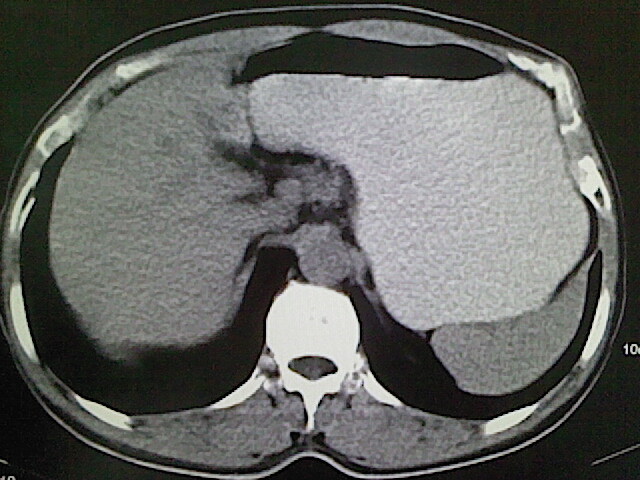

标题: CT18630:男,54岁,乙肝,大家看怎么样? [打印本页]

男,54岁,乙肝,大家看怎么样?

肝脏的要有增强敢说话

未见明确异常;建议必要时行ct增强扫描检查。